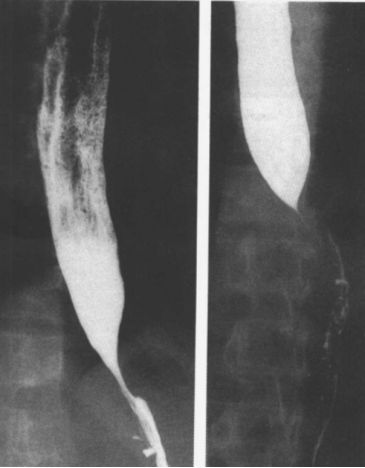

食管静脉曲张:蚯蚓样、串珠状。

食管重度静脉曲张

食管静脉曲张:食管黏膜呈现蚯蚓状

这是食管静脉曲张伴胃底静脉曲张的图像